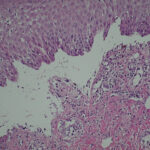

Histopathology. The bullous pemphigoid-like presentation described above is the most common form of EBA. The subepidermal blisters are inflammatory. The predominant infiltrating cells are lymphocytes and neutrophils in perivascular and focal interstitial array. Eosinophils are present in variable numbers . In the classic form, the subepidermal blisters are noninflammatory ; fibrosis and milia formation are often present. |